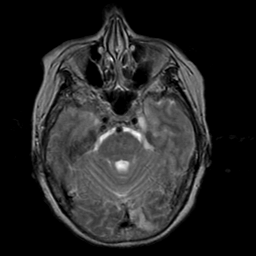

Stroke:T2-weighted MR #2 -- Slice #7

[Home][Help][Clinical] Slice 7